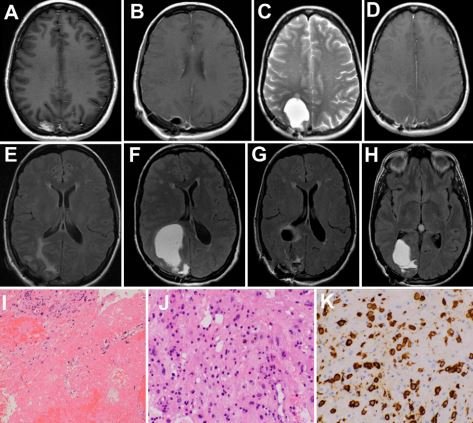

SRS carries a risk of late cyst development in AVMs - years post treatment - but is the same true for #brainmets? Here we show a similar phenomenon in long-term survivors, a steadily growing population. #cancersurvivorship Journal of Neurosurgery #btsm thejns.org/caselessons/vi…

SRS carries a risk of late cyst development in AVMs -  years post treatment - but is the same true for #brainmets? Here we show a similar phenomenon in long-term survivors, a steadily growing population. #cancersurvivorship <a href="/TheJNS/">Journal of Neurosurgery</a> #btsm

thejns.org/caselessons/vi…